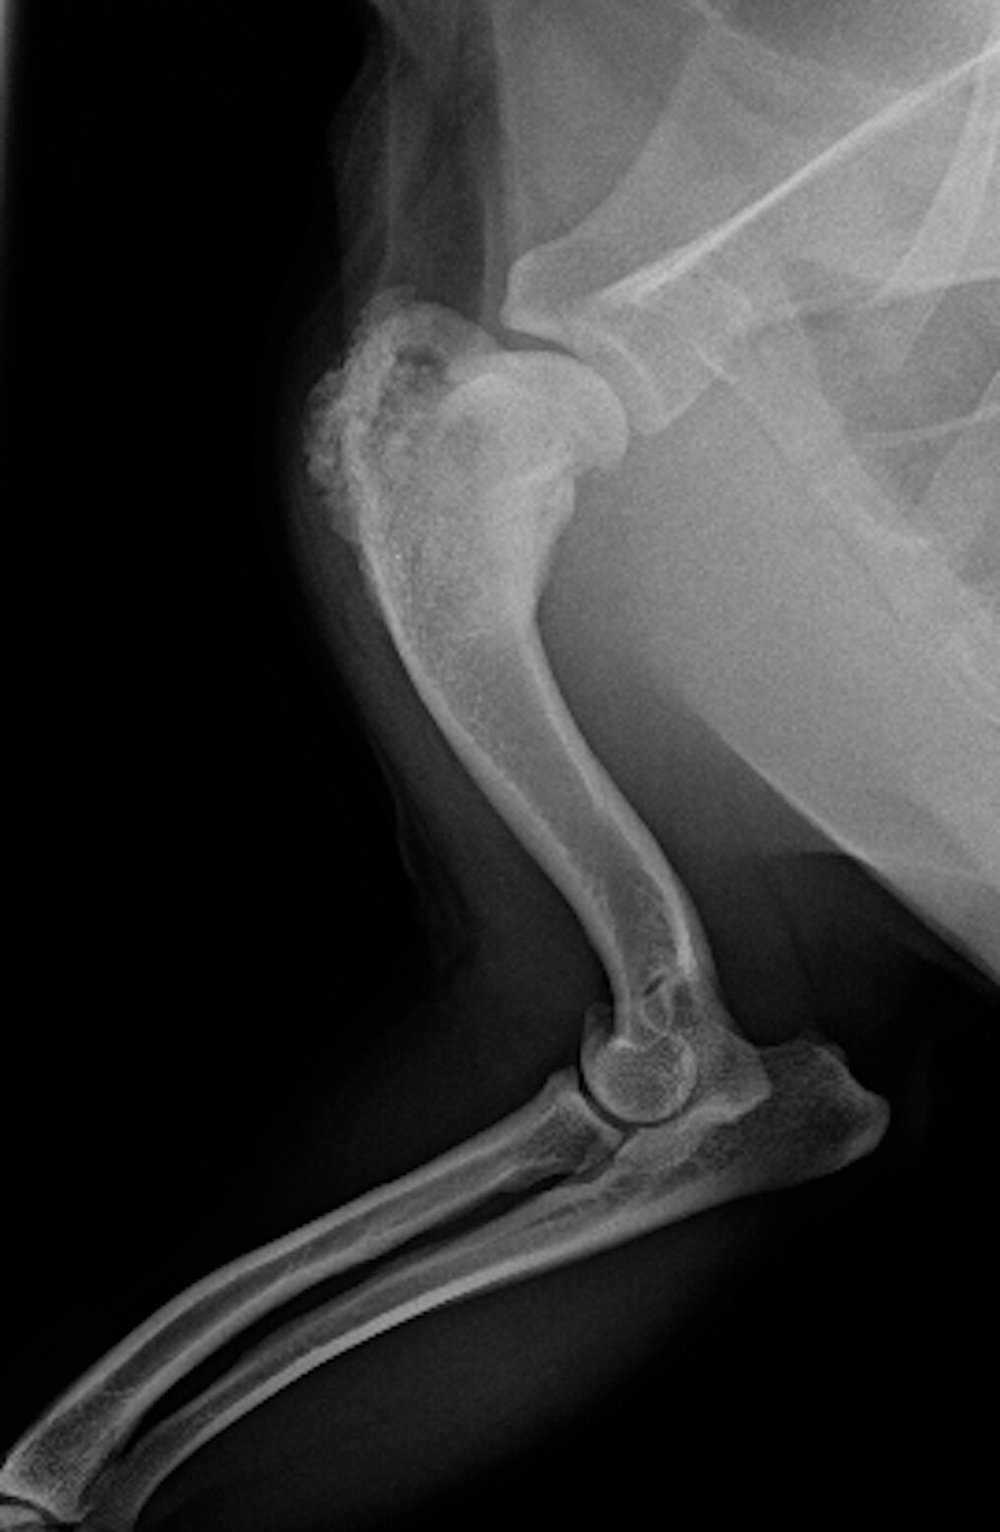

. How long does bone cancer take to kill a dog Tuesday July 12 2022 The average survival time in dogs with osteosarcoma treated with surgery and chemotherapy is. How long does a potentially splintering bone take to kill a. Bone tumors in dogs and cats can arise in any bone of the body including the long bones within limbs toes spinal vertebrae ribs and the skull.

Potential causes of bone cancer The causes of canine osteosarcoma are unknown. Osteosarcomas do this frequently. It is the most common primary bone cancer in dogs and typically occurs in the leg.

This high local dose of cisplatin will kill the remaining cancer cells in the leg. This is the most common sign that the dying process has. Osteosarcoma is an aggressive cancer arising from the bone.

Eventually the limbs become so weak they will break and injure easily. Without treatment a dog diagnosed with osteosarcoma will succumb to the cancer in only one to two months. It can affect any dog and seems to be quite prevalent in larger breeds such as Irish wolfhounds greyhounds Rottweilers and great Danes.

In a period of three months the tumor can overtake the dogs limb and weaken it. Bone cancer in dogs can quickly spread to other organs. How can you tell if a dog is dying from cancer.